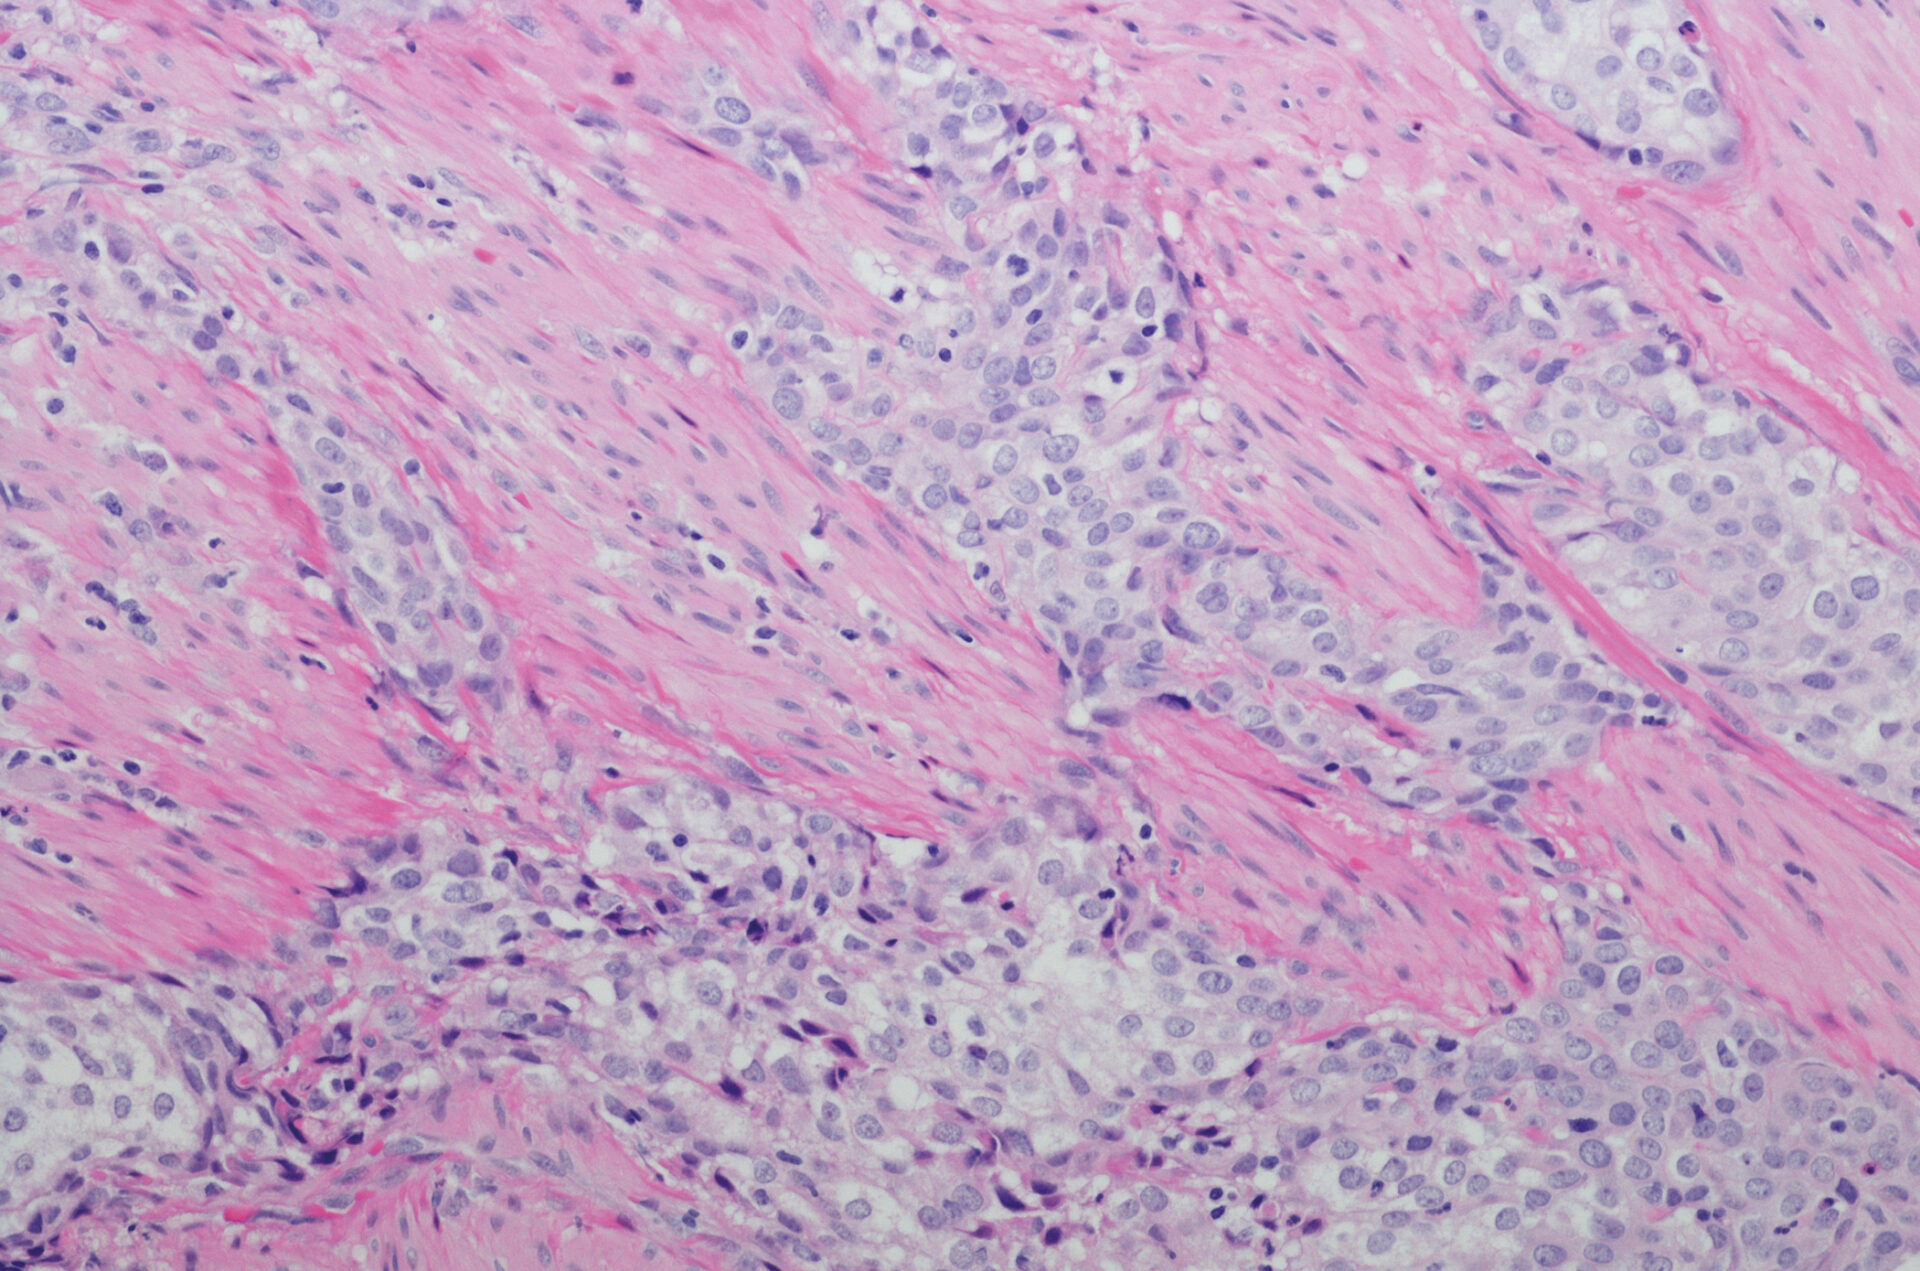

Das Harnblasenkarzinom gehört zu den häufigen maligen Erkrankungen. Während bei oberflächlichen Tumoren die Prognose der Patienten in der Regel günstig ist, sieht es beim muskelinfiltrierenden und organüberschreitenden Urothelkarzinom deutlich schlechter aus. Doch es tut sich was im Therapiemanagement des fortgeschrittenen/metastasierten Blasenkarzinoms. Vor allem die Behandlung mit Immuncheckpoint-Inhibitoren zeigt sich nach radikaler Resektion hoch wirksam.